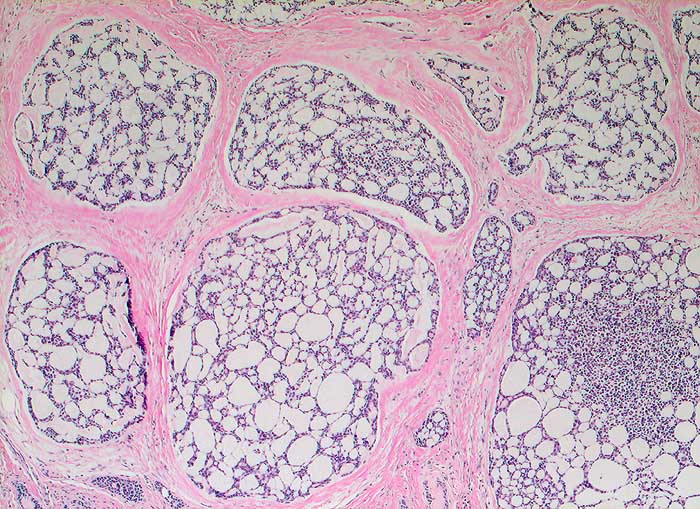

Adenoidzystisches Karzinom der Mamma

Adenoidzystische Karzinome machen lediglich 1% aller Mammakarzinome aus. Die Morphologie ist identisch mit dem gleichnamigen Tumor der Speicheldrüsen. Die Zellen des adenoidzystischen Karzinoms bilden kohäsive Verbände und Drüsen oder mikrozystische Strukturen. Die Tumorzellen sind klein und monomorph, die Kern-Zytoplasmarelation ist hoch. Die Kerne sind dunkel, rund bis oval oder angulär und enthalten bisweilen einen kleinen Nukleolus. Azelluläre hyaline Körperchen aus mucoidem Material, welche die Hohlräume der intakt aspirierten kribriformen Strukturen ausfüllen, sind besonders typisch. Das mucoide Material kann auch verzweigte oder fingerartige abgerundete Strukturen ausbilden.